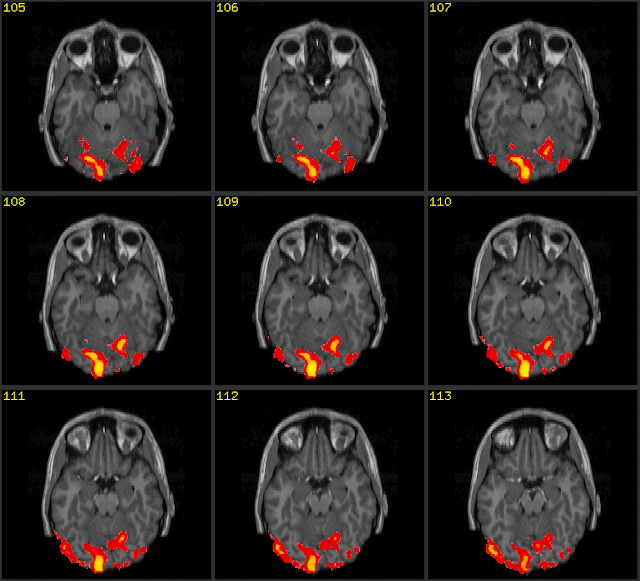

Discovery of Using fMRI to Interpret Human Thoughts. An epiphany of Donald H Marks